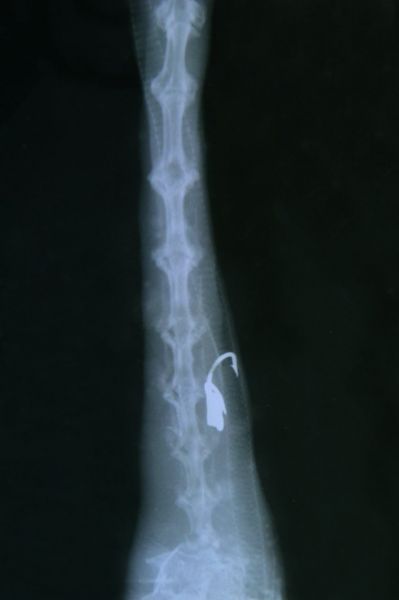

Zwerfvuil bezoedelt niet alleen onze wegbermen, parken, bossen en natuurgebieden, maar heeft ook een rechtstreekse impact op wilde dieren. Regelmatig worden we in het Natuurhulpcentrum geconfronteerd met 'zwerfvuilslachtoffers'.

* Watervogels die verstrikt zitten in rondslingerende visdraad.

* Dieren die plastic of ander afval mee opeten.

* Vogels die slierten plastic of touw meenemen naar hun nest en daarin verstrikt geraken.

* Dieren die zich kwetsen of komen vast te zitten omdat ze restjes uit blikjes of bokalen willen snoepen

Wilde dieren kunnen zich op die manier ernstig kwetsen en zelfs sterven.